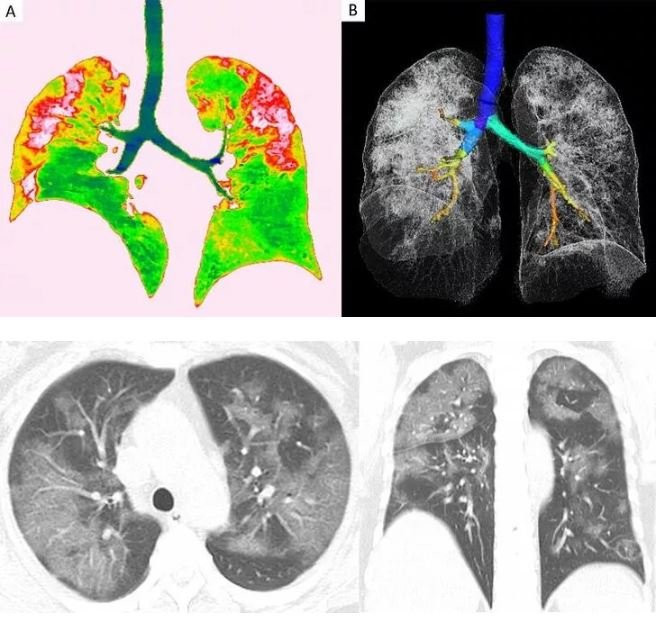

Sağlık Bilimleri Üniversitesi Gülhane Eğitim ve Araştırma Hastanesi'nde Covid-19 tedavisi gören hastaların akciğerlerindeki tahribat, tomografi görüntülerine yansıdı. Görüntülerde, hastalığın ne kadar hızlı ilerlediği, akciğeri nasıl tuttuğu ve yarattığı hasar gözler önüne serildi. Göğüs Hastalıkları Uzmanı Doç. Dr. Cantürk Taşçı, Covid-19'un akciğere girişini ve bıraktığı hasarı anlattı.

Doç. Dr. Taşçı, koronavirüsün akciğerdeki solunum keseciklerinde hasara yol açtığını kaydederek, "Orada bir sertleşme, büzüşme, solunum keseciklerinin fonksiyonlarını yitirmesine neden oluyor. Bu, yaygınlığı, şiddeti arttıkça hastaları solunum yetmezliğine götürebiliyor. Ama dediğim gibi her hastada farklı seyretmekte. Hastanın kendi bağışıklık sisteminin gücüyle beraber bazı hastalarda solunum yetmezliğine, bir kısım hastada yoğun bakıma kadar ilerleyebilmekte.Bazı hastalarda çok yaygın akciğer büzüşmesi denilen tabloya yol açıyor. Tabii ki bu hastaları biz yine iyileştiklerinde taburcu ediyoruz; ama akciğerdeki düzelmeler akciğer büzüşmesi oluştuysa ayları bulabiliyor. Onun dışında o kadar şiddetli değilse taburcu olduktan yaklaşık 1 hafta 10 gün sonra akciğerleri tamamen normale de dönebiliyor. Akciğerde kalıcı hasar şu ana kadar gördüklerimizde yok. Hastaları kontrollere çağırıyoruz, akciğer hasarı takiplerimizde hemen hemen yok" ifadelerini kullandı.